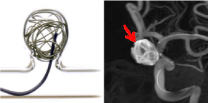

⾎管撮影検査

当院は全国循環器撮影研究会による施設認定(被ばく線量低減推進施設認定)を受けているとともに、⾎管造影・インターベンション専⾨診療放射線技師の認定を受けたスタッフを中⼼として、精度管理ならびに被ばく低減を⼼掛け検査に従事しています。

●⾎管塞栓術

動脈瘤、がん、外傷に伴う出⾎などに対してコイルを始めとする各種の機器や器具、塞栓物質を使⽤することで⾎流を遮断し出⾎を防ぎます。